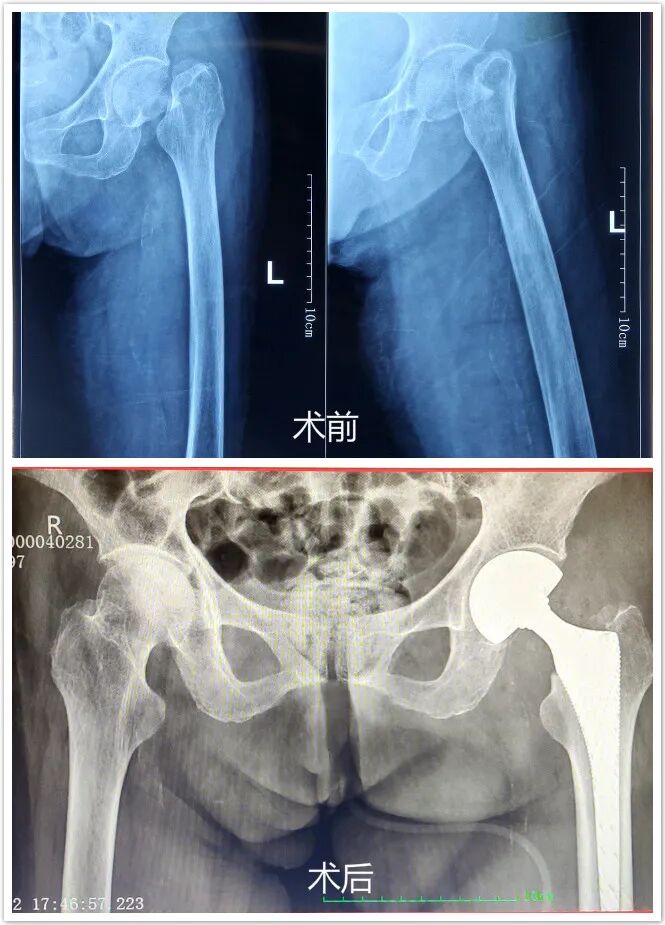

今年是孔奶奶101岁生辰,在这举家欢喜之际,老太太却意外摔了一跤,造成了左侧骨颈骨折(头下型)。

在完善术前准备后,骨科团队为患者实施了股骨头置换术。术中进展顺利,出血少,仅用了四十多分钟就顺利完成。